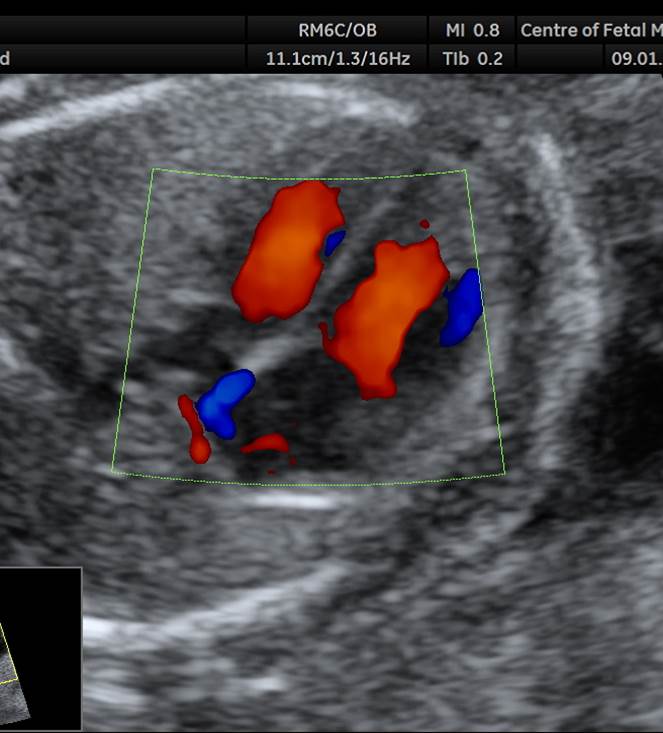

- У плода стеноз легочного ствола. На 4камерном срезе сердца обращает на себя внимание утолщение миокарда правого желудочка. В срезе через правый выходной отдел видно сужение легочного ствола на уровне клапана и постстенотическое расширение. В режиме ЦДК определяется антеградный турбулентный кровоток в легочном стволе.